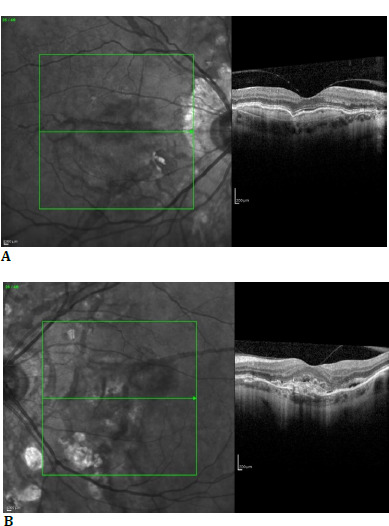

Case report: A 46-year-old patient presented for progressive loss of vision and metamorphopsias in the left eye. The ophthalmological examination showed angioid streaks and secondary choroidal neovascularization. The dermatologist performed an incisional biopsy of a skin area in the right axilla that showed white-yellow, discrete streaks. Histopathological examination confirmed the diagnosis of pseudoxanthoma elasticum. It was decided to start intravitreal injections with aflibercept. Three injections were made in the left eye with subsequent visual acuity improvement.